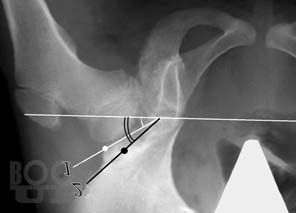

В монографии представлены методики диагностики и хирургического лечения дисплазии тазобедренного сустава у детей. Описана и дана сравнительная оценка современных методов оперативного лечения данной патологии с подробным изложением техники вмешательств на тазовом и бедренном компонентах сустава. Отражена методика послеоперационного реабилитационного периода.